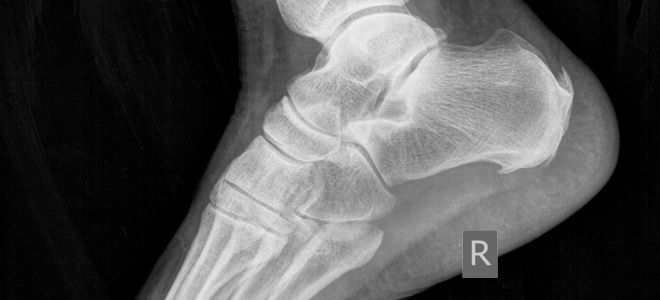

Термин «пяточная шпора» обозначает воспаление подошвенной фасции, которая представляет собой мощную пластину, расположенную в области внутреннего свода стопы. Она начинается от верхней части пяточной кости и простирается по всей подошве, охватывая мышцы, и прикрепляется к плюсневым костям. Эта фасция всегда находится в натянутом состоянии, что позволяет ей:

Таким образом, подошвенная фасция играет важную роль в защите суставов и костей стопы от избыточного давления и травм. Воспаление или повреждение этой структуры может вызывать сильные болевые ощущения, что заставляет пациента менять привычный образ жизни. Для того чтобы устранить данную патологию, необходимо точно определить ее причину, что можно сделать с помощью аппаратных методов исследования.